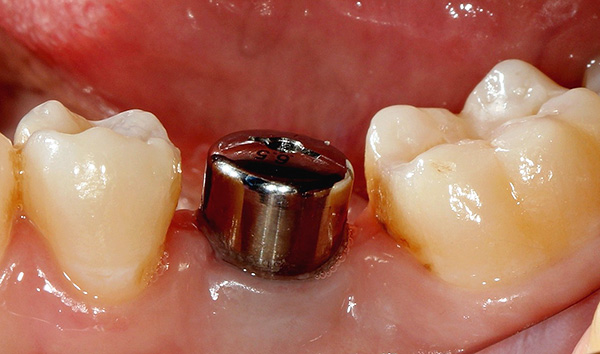

As fotos abaixo mostram os implantes removidos: